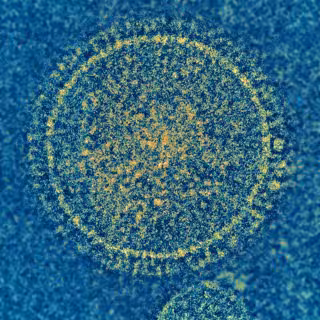

Virus sincitial respiratorio

NIAID - Archivo